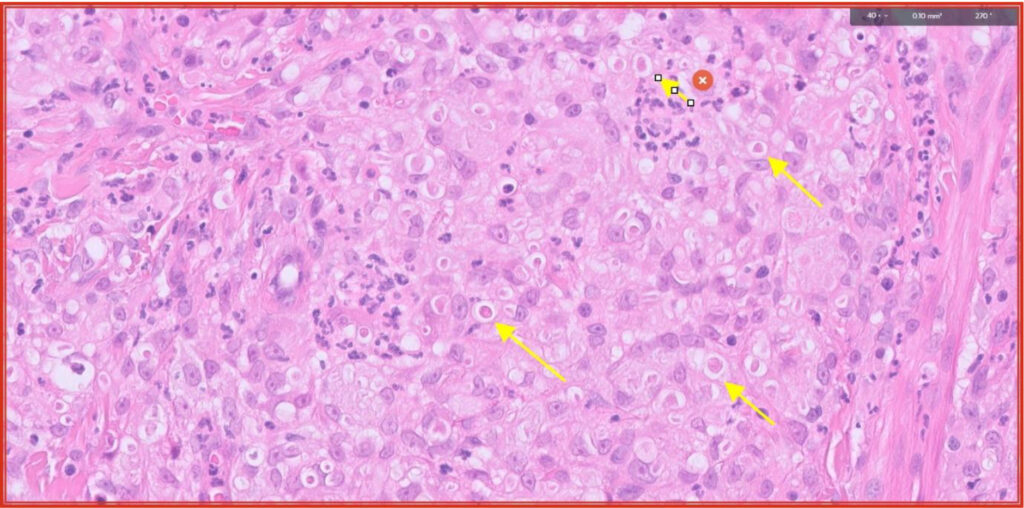

Fig 7. Pyogranulomatous dermatitis with yellow arrows highlighting intralesional fungal organisms (same area as red box in Fig 5).

Fig 8. PAS stain highlights the fungal organisms (yellow arrows). They are most likely opportunistic fungi but fungal culture would be required to identify them definitively.